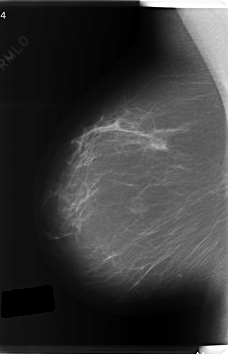

C_0219_1.RIGHT_CC

RIGHT_MLO LINES 6040 PIXELS_PER_LINE 3864 BITS_PER_PIXEL 12 RESOLUTION 50 NON_OVERLAY